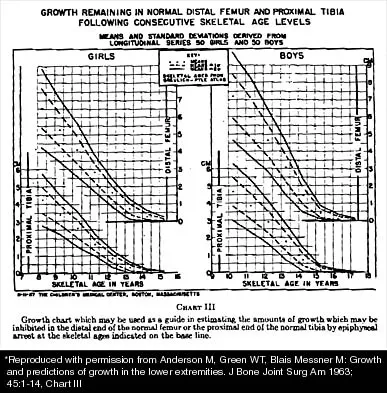

A 10-year-old girl with a monoarticular pattern of juvenile rheumatoid arthritis (JRA) has had a 3-cm limb-length discrepancy since age 8 years when inflammation in the right knee came under good medical control. Because her right leg is longer, the patient states that she would like her legs to be close to equal in length in the future. A growth-remaining chart is shown in Figure 14. Management should consist of

Explanation